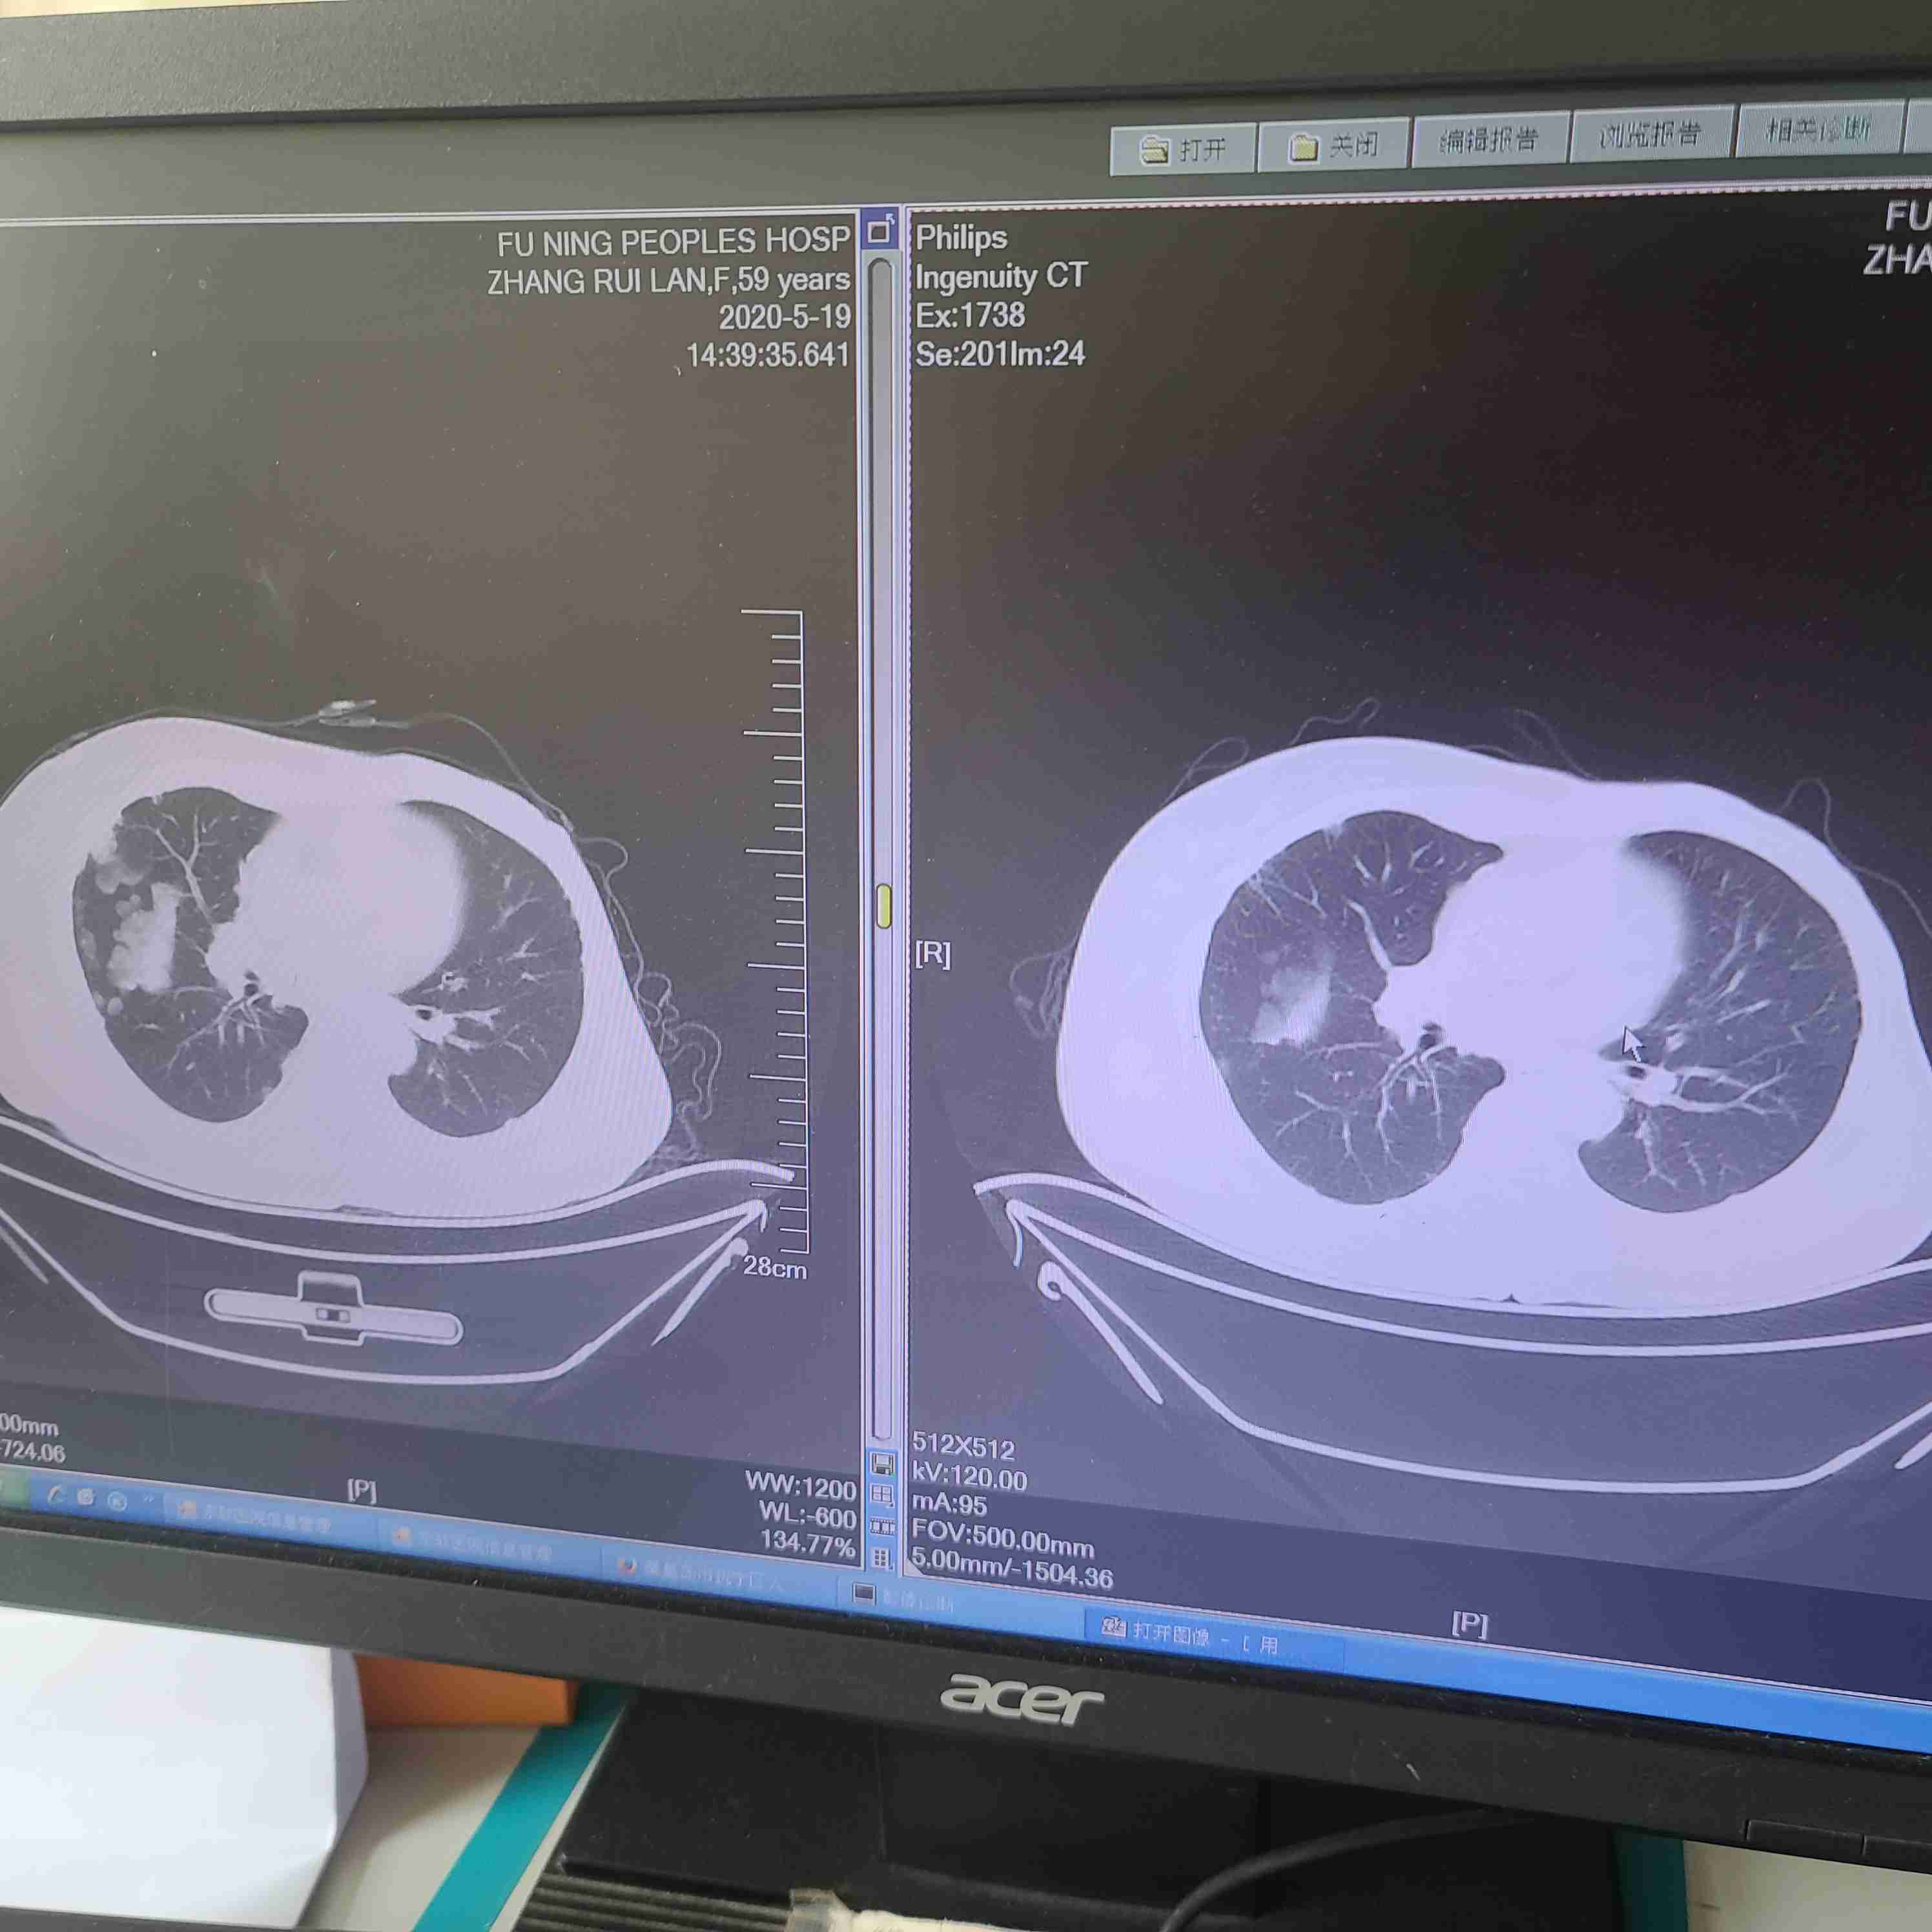

百善孝为先 02022-09-20父亲一个半月前检查出肺癌晚期脑转移压迫神经线,已经切除脑肿瘤现恢复良好,现在很迷茫不知道该如何进行下一步的治疗,跪求大家...

向日葵,的太阳 02022-09-06我父亲肺腺癌,目前检测出来的结果是双肺门和纵隔淋巴结可能转移的结果,基因检测无靶向药。有什么好建议,请大家提提建议。